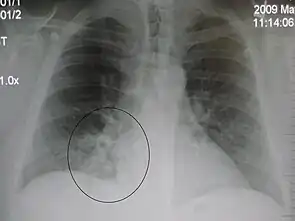

AP CXR showing left lower lobe pneumonia associated with a small left sided pleural effusion

AP CXR showing right lower lobe pneumonia

AP CXR showing pneumonia of the lingula of the left lung

Right upper lobe pneumonia as marked by the circle.

Left upper lobe pneumonia with a small pleural effusion.